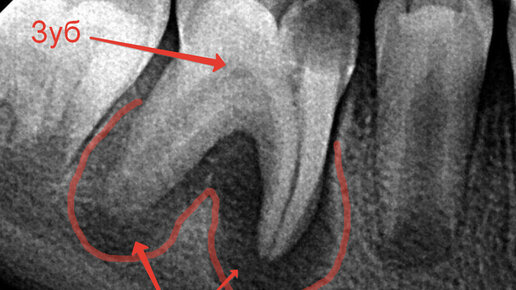

Это самый частый вопрос от пациентов, у которых на корне зуба обнаружили воспаление. И этот вопрос вполне логичный. Воспалительный очаг на верхушке корня, или в простонародье, киста, как правило, является осложнением кариеса и главной причиной потери зубов. Перед пациентом стоит выбор: удаление зуба с последующим протезированием или лечение такого зуба, но без каких-либо гарантий. По сути, выбираем между плохим или очень плохим вариантом. Коллегам сразу скажу, что я знаю, что киста- гистологический диагноз и правильнее говорить периодонтиты, очаги деструкции и т...

Сегодня мы с вами разберем одну из самых частых причин потери зубов – периодонтиты(или, как вы иногда их называете, «кисты», хотя это совсем про другое), то есть воспаление связки, в которой сидит зуб. Про строение зуба можно почитать тут. Основных причин воспалений этой связки, как правило, три. 1 . Инфекция, как осложнение кариеса. Помним нашу горную деревушку из главы 48? Сага о стоматологии. Глава 48. Что делать если сильно болит зуб ночью? Когда кариозная полость доходит до нерва, то инфекция начинает его убивать...